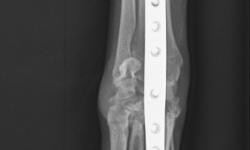

Pacient č.: 1. - rtg po operaci.

Pacient č.: 2. - pooperační rtg.

Pacient č. 3. - pooperační rtg.

Pacient č. 3. - po operační rtg 2.

Pacient č. 3. - pooperační rtg, stav po osmi měsících.

Pacient č. 3. - pooperační rtg 2., stav po osmi měsících.